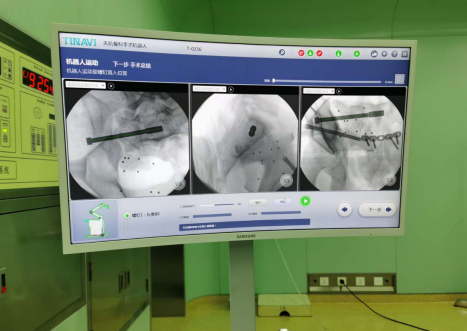

夏建军医生介绍,这次手术需要对骶髂关节分离固定,在完成耻骨结节固定后,通过机器人规划右侧前柱通道螺钉和右侧骶髂螺钉路径,进行手术固定。首先要完成对骨盆的三维扫描,并将影像数据传输到机器人的“大脑”;医生根据扫描影像完成置入位置、方向以及长度等手术规划;然后在骨科机器人的精确定位下,夏建军医生沿着套筒钻入导针,确认位置无误后,再沿导针打入螺钉固定,拔出导针;最后再次扫描手术区,螺钉位置与既定规划一致。从侧面看,骶髂关节处的螺钉只有一个小圆点,定位精准,髋臼前柱骨折间隙缩小、骶髂关节间隙正常,固定稳定,术中软组织损伤少,手术切口小、安全性高。如果用传统手术方式需要开一个至少20厘米左右的创口,不仅创伤大,而且螺钉定位也很难做到精准,且患者恢复缓慢。由于天玑骨科手术机器人定位精准,无需在术中多次透视来确定螺钉位置,大大减少了术中辐射量。